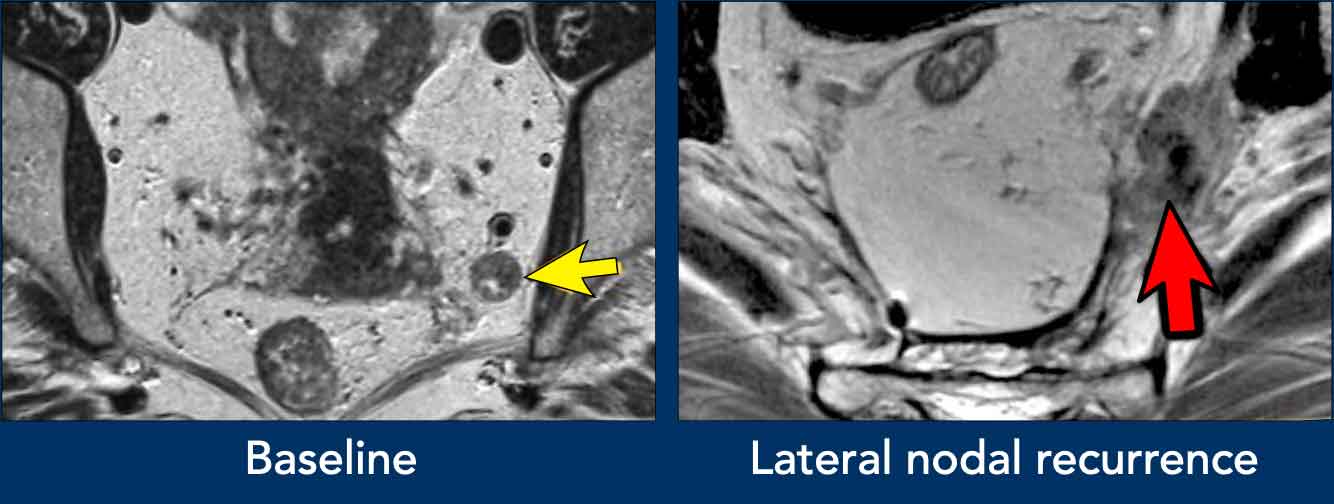

Lateral lymph nodes (internal iliac/obturator)

Internal iliac and obturator lateral lymph nodes are primarily assessed by size, with ≥7 mm (short axis) as the main criterion for cN+.

Morphologic features—indistinct borders, heterogeneous signal, round shape, and loss of fatty hilum—can support malignancy in intermediate-sized (5–7 mm) nodes, especially if multiple or in the presence of other clearly pathologic lateral nodes.

Reporting Requirement

Any lateral N+ nodes (though included in the overall cN-category) must be highlighted separately in the MRI report, with location and size specified, as these require targeted treatment to prevent lateral recurrence.

Images

• Left image: Pathologic 9 mm lymph node in the left obturator space (arrow), identified at baseline staging. Requires irradiation and/or separate resection to avoid lateral recurrence.

• Right image: Patient treated with standard TME (without lateral nodal resection) who developed an irregular mass in the left obturator space, consistent with lateral nodal recurrence.